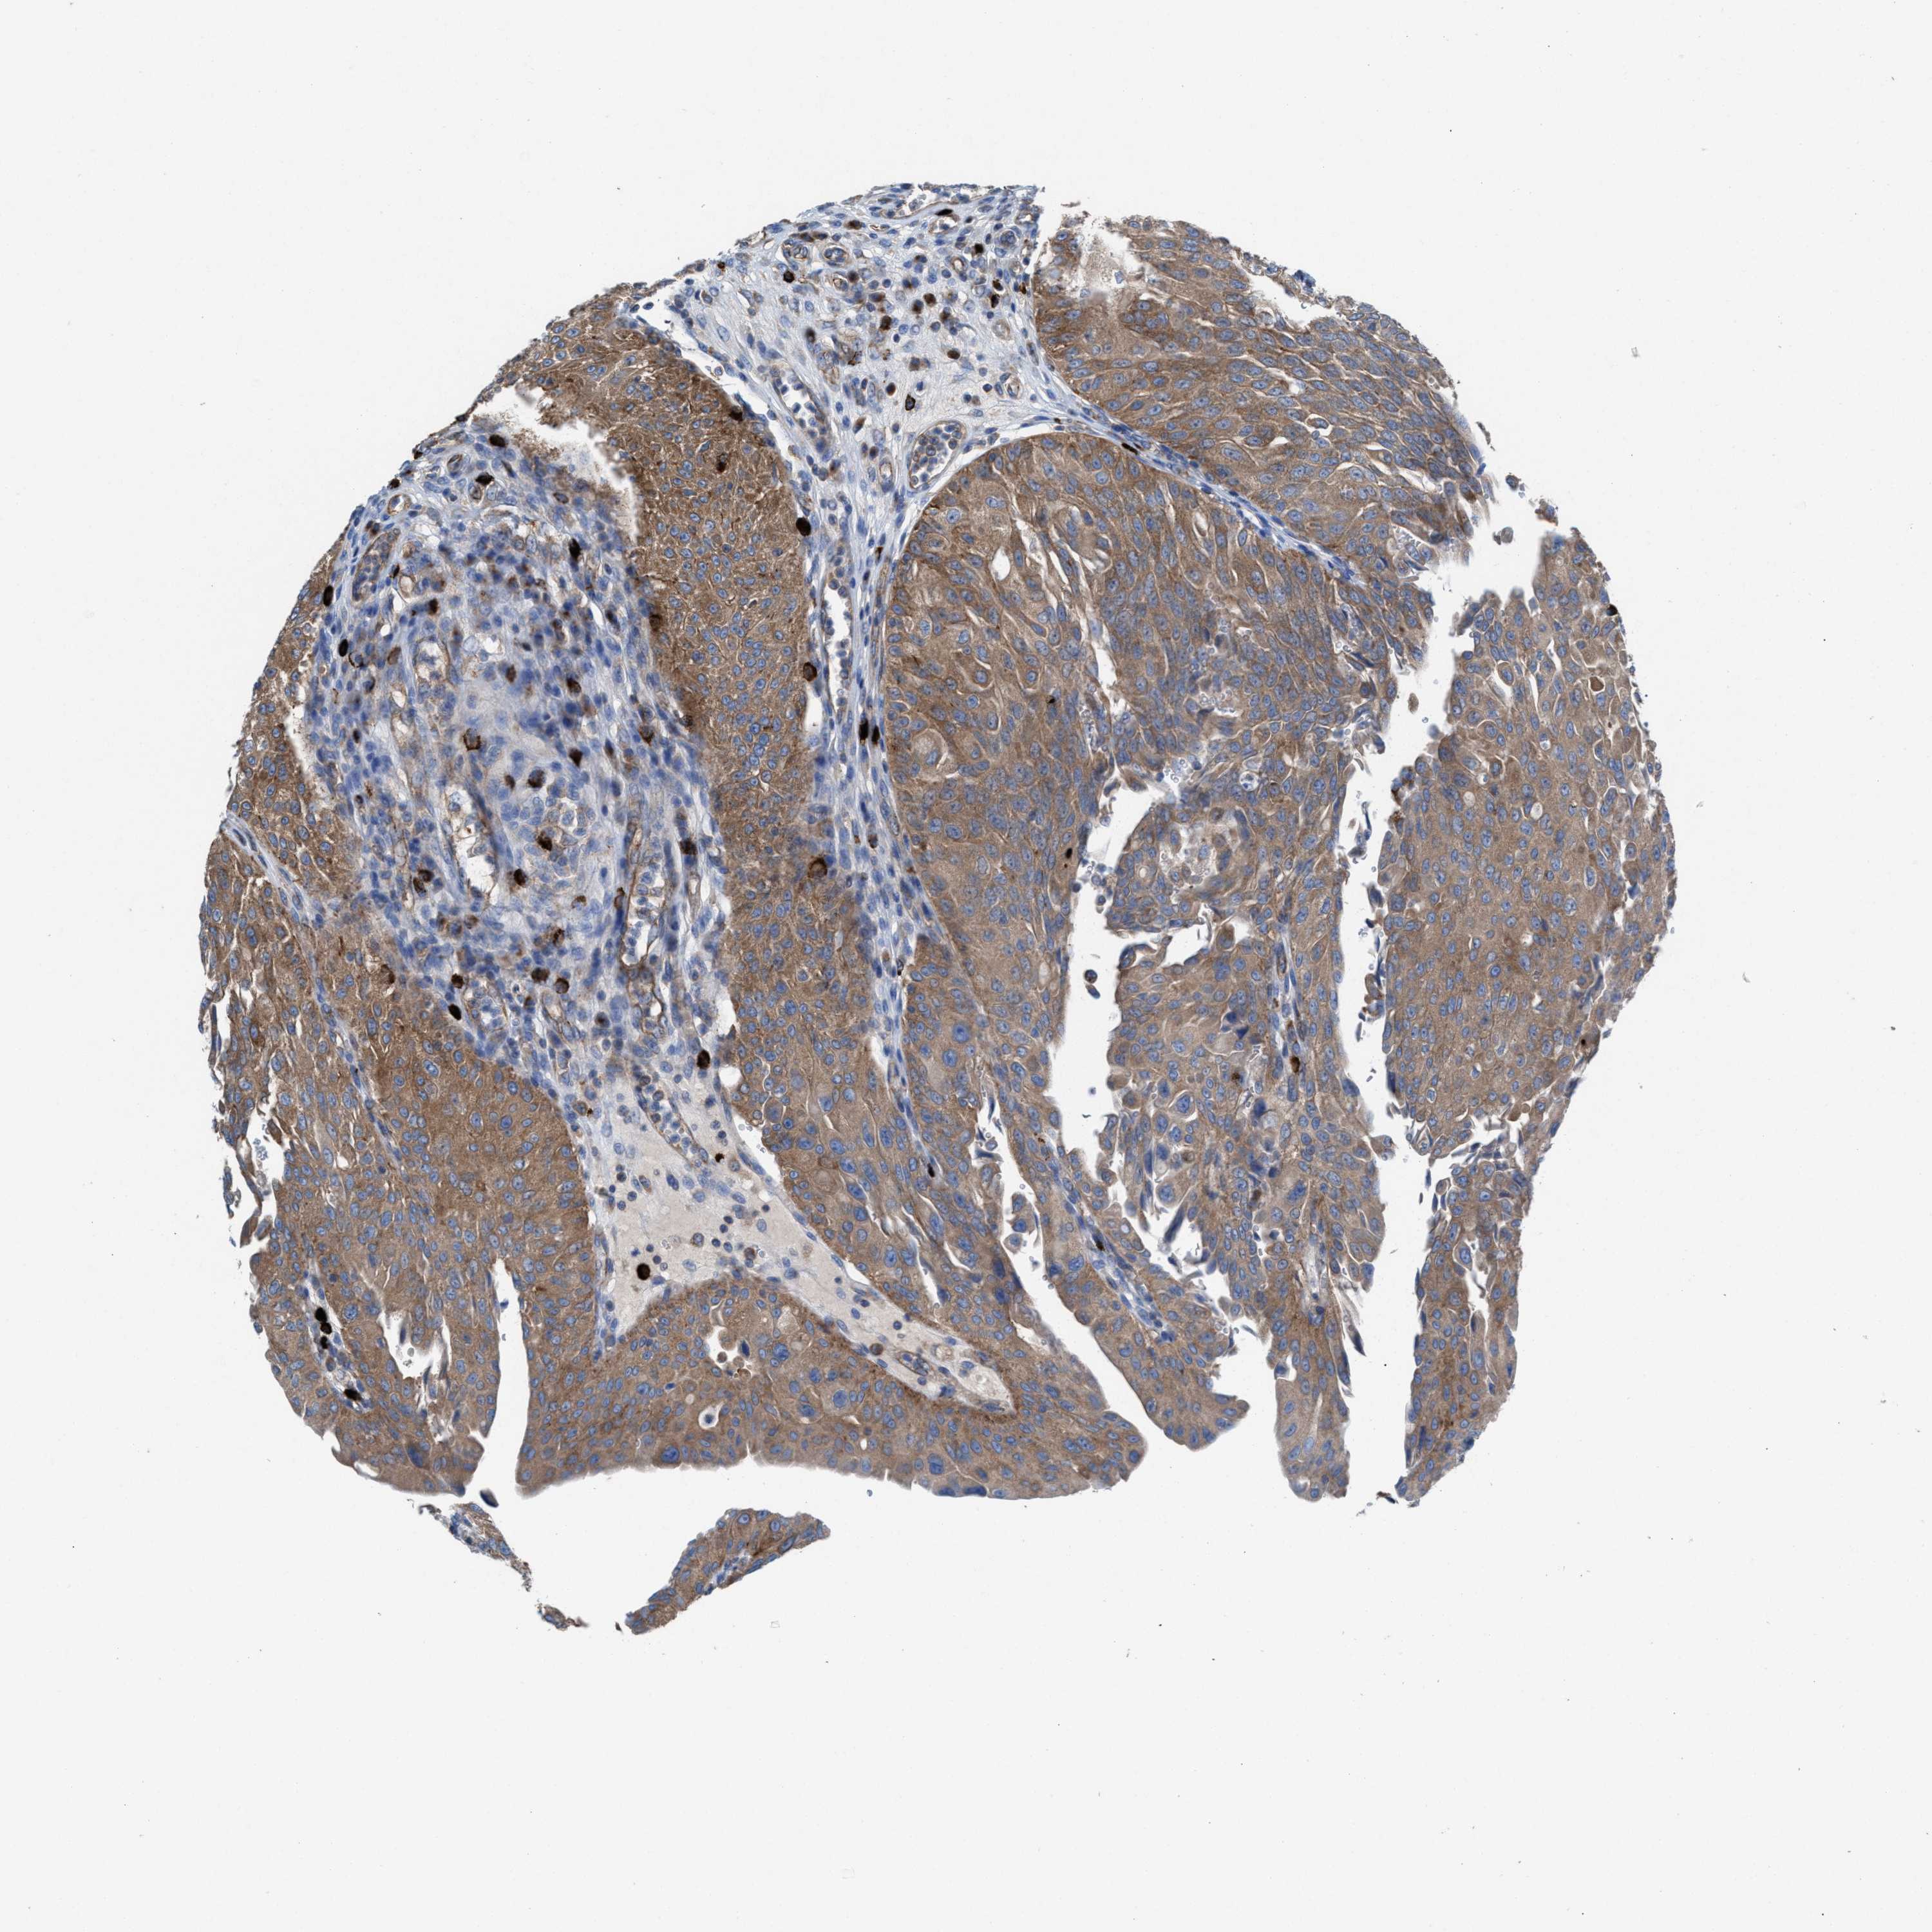

UROTHELIAL CANCER - Protein expressioni

A mouse-over function shows sample information and annotation data. Click on an image to view it in a full screen mode. Samples can be filtered based on level of antibody staining by selecting one or several of the following categories: high, medium, low and not detected. The assay and annotation is described here.

Note that samples used for immunohistochemistry by the Human Protein Atlas do not correspond to samples in the TCGA dataset.

Antibody stainingi

Antibody staining in the annotated cell types in the current human tissue is reported as not detected, low, medium, or high, based on conventional immunohistochemistry profiling in selected tissues. This score is based on the combination of the staining intensity and fraction of stained cells.

Each image is clickable and will lead to virtual microscopy that enables deeper exploration of all samples and also displays staining intensity scores, fraction scores and subcellular localization as well as patient and tissue information for each sample.

Antibody HPA022251

Staining

High

Medium

Low

Not detected

Intensity

Strong

Moderate

Weak

Negative

Quantity

>75%

75%-25%

<25%

None

Location

Nuclear

Cytoplasmic/membranous

Cytoplasmic/membranous,nuclear

Urothelial carcinoma, Low grade

Urothelial carcinoma, High grade